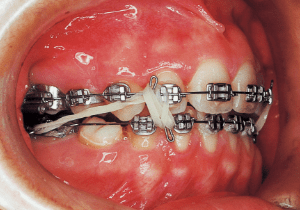

8 3-23-’87 Treatment Progress

The treatment progressed more favorably than anticipated, with the open bite and Class II malocclusion nearly resolved within five months of treatment initiation. However, discontinuing the use of rubber bands often resulted in an open bite.